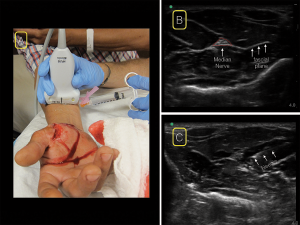

The median nerve lies along the midline of the forearm in the fascial plane between the flexor digitorum superficialis and profundus tendons. Place the linear ultrasound probe in a transverse position at the wrist crease on the volar surface of the distal forearm. Scan proximally to the mid-forearm and look for the classic “honeycomb” appearance of a nervous structure at the junction of several fascial planes (see Figure 3). There are no associated vascular structures, except in rare incidences. In the distal wrist, muscle tendon sheaths will look similar to the classic honeycomb appearance of the nerves. By scanning proximally, tendons will disappear and the nerve will be clearer.

Figure 3. For the median nerve block, place the linear ultrasound probe in a transverse position at the wrist crease on the volar surface of the distal forearm. Scan proximally to the mid-forearm (A) and look for the classic “honeycomb” appearance of a nervous structure at the junction of several fascial planes (B). insert your needle from whichever side is most comfortable (A&C).